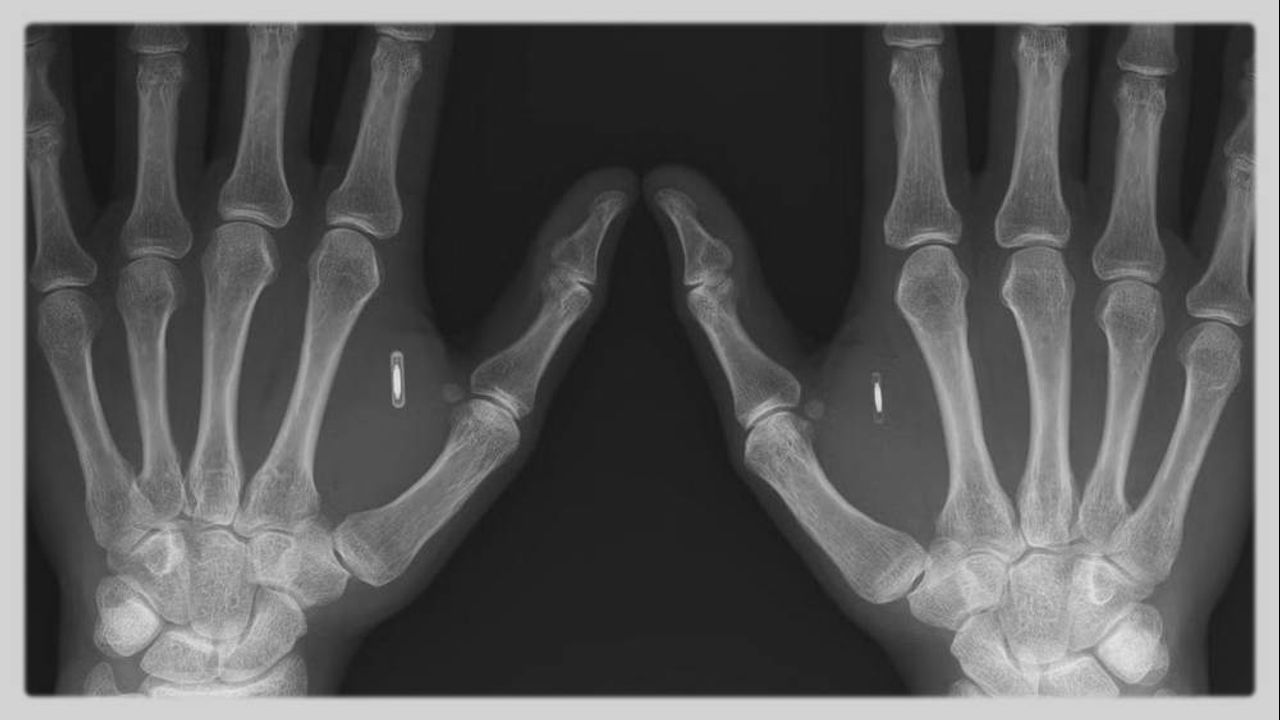

Banking Insider Warns CBDCs Will Be Implanted Chips